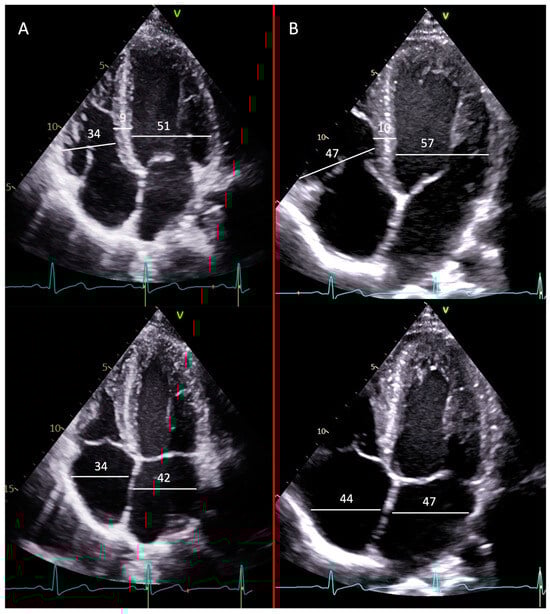

4. Transthoracic Echocardiogram